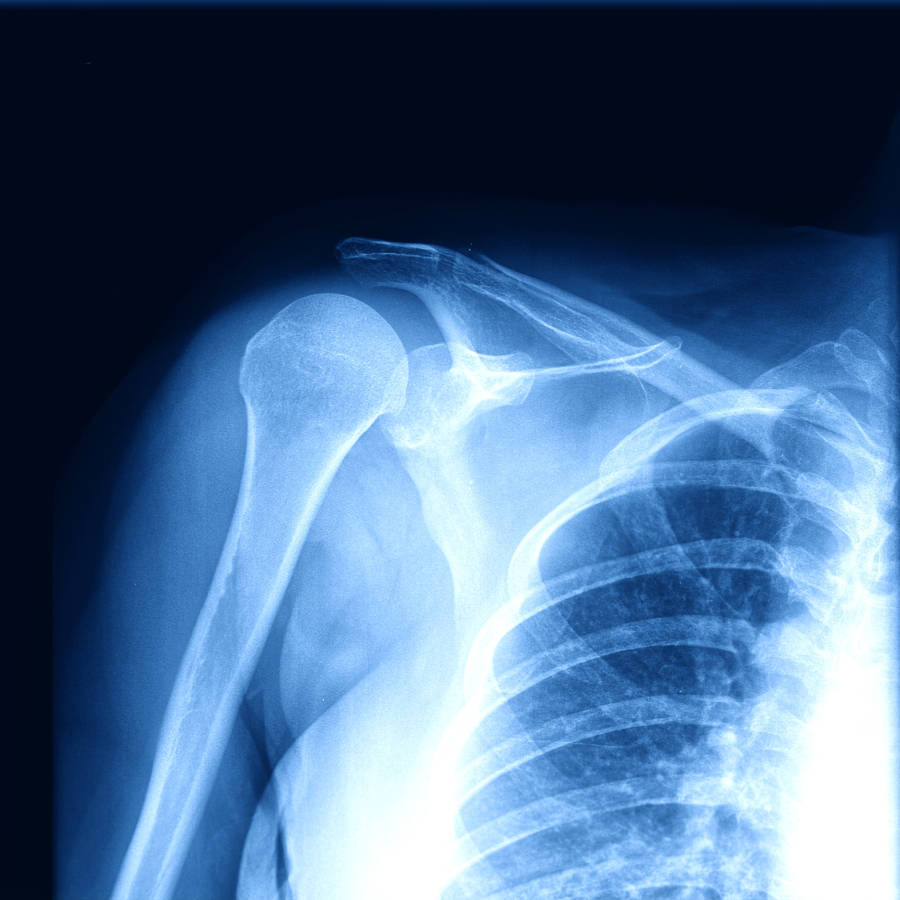

Hombro